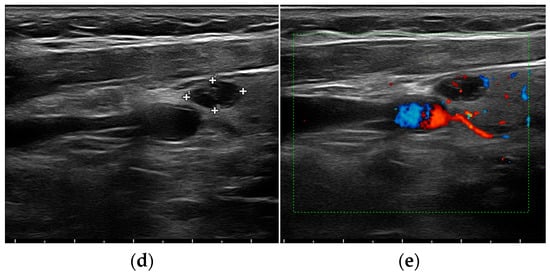

- Mohammadi, A.; Moloudi, F.; Ghasemi-rad, M. The role of colour Doppler ultrasonography in the preoperative localization of parathyroid adenomas. Endocr. J. 2012, 59, 375–382. [Google Scholar] [CrossRef]

- Vitetta, G.M.; Ravera, A.; Mensa, G.; Fuso, L.; Neri, P.; Carriero, A.; Cirillo, S. Actual role of color-doppler high-resolution neck ultrasonography in primary hyperparathyroidism: A clinical review and an observational study with a comparison of (99m)Tc-sestamibi parathyroid scintigraphy. J. Ultrasound. 2019, 22, 291–308. [Google Scholar] [CrossRef]

- Liu, H.; Liao, Q.; Wang, Y.; Hu, Y.; Zhu, Q.; Wang, L.; Liu, Q.; Li, J.; Jiang, Y. A new tool for diagnosing parathyroid lesions: Angio plus ultrasound imaging. J. Thorac. Dis. 2019, 11, 4829–4834. [Google Scholar] [CrossRef]